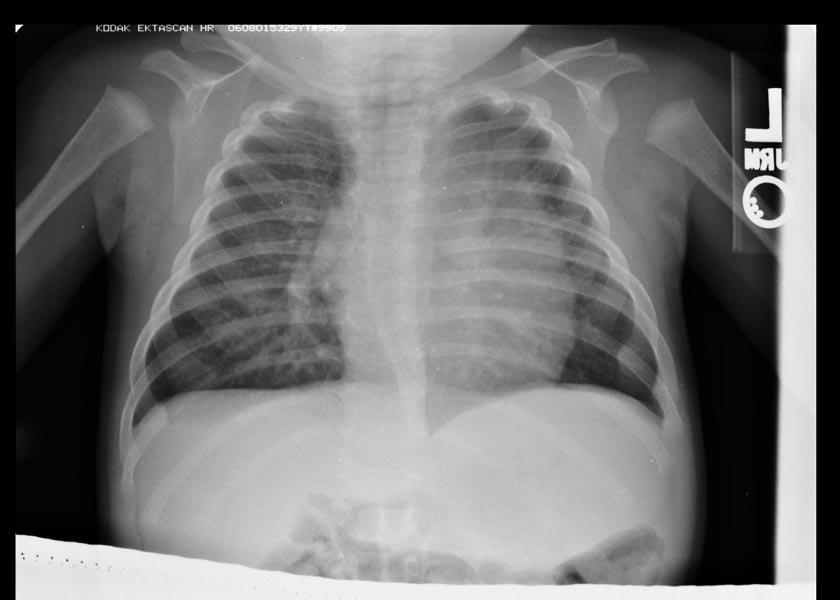

Тимомегалия: что это такое и как проявляется